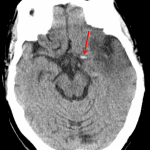

- Asymmetric increased density of the left carotid terminus and proximal left M1 segment

Asymmetric increased density of the left carotid terminus and proximal left M1 segment, likely representing thrombus.

- The earliest CT finding of MCA territory ischemia is a dense MCA sign (seen immediately), though this is seen in a minority of cases